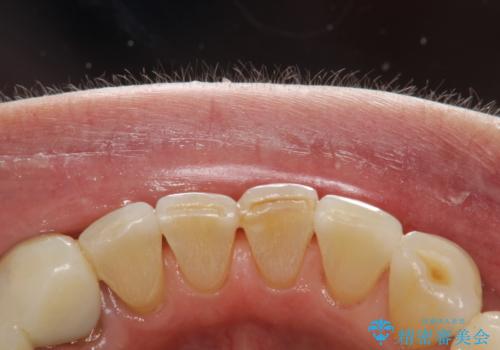

インビザライン中に歯の着色落としクリーニング PMTC

- インビザライン治療中に着色が気になるとのことでクリーニングを希望されました。PMTC30分コースを行いました。

インビザライン治療中には、歯の表面にアタッチメント(効率的に歯の移動をするもの)を設定します。そのため歯ブラシでは届きにくい細かい部分などに、歯石や着色がついてしまうことがあります。着色などを放置していると、着色なのか、虫歯なのかの判別もしずらく正確にお口の中の状態を診断できません。

矯正治療中も定期的に歯科医院にてPMTCを受けて、お口のケアを行うことをおすすめします。